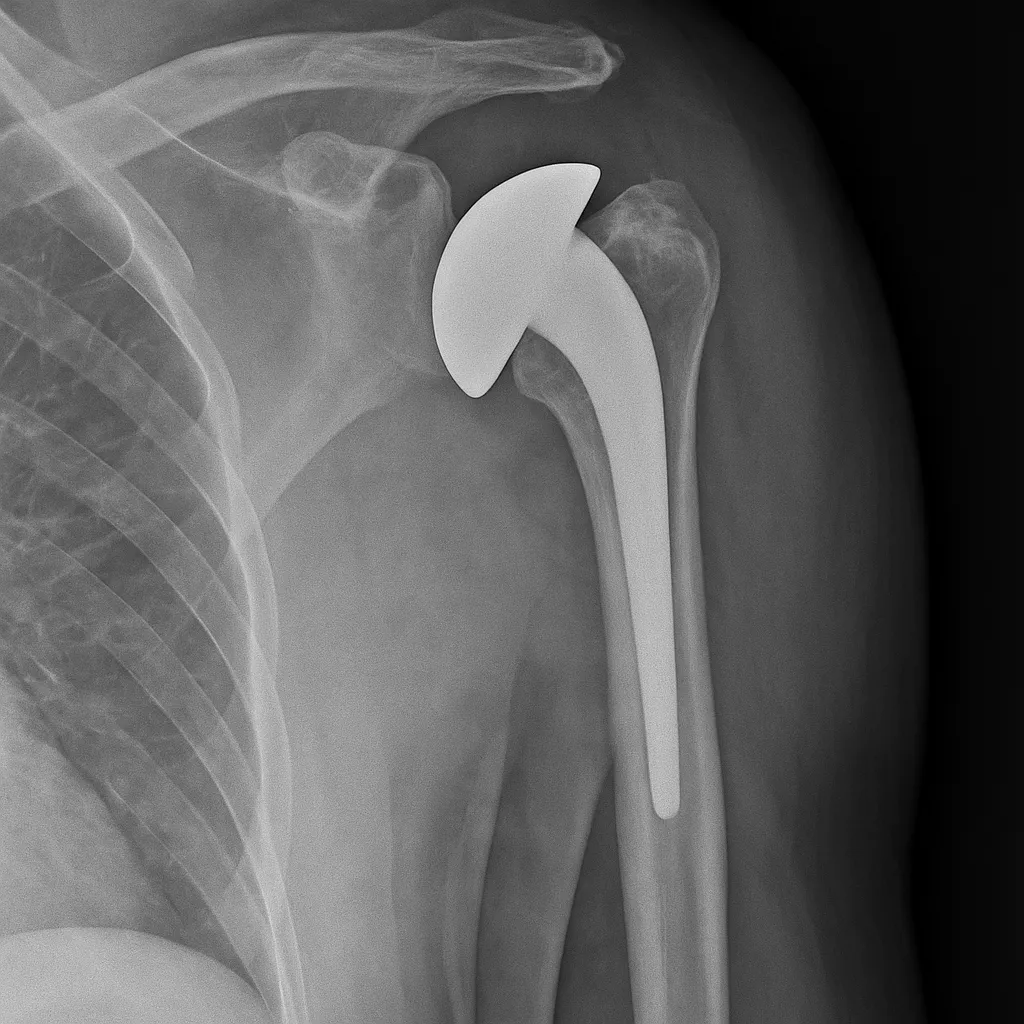

Anatómiás vállízületi protézis

Ez az implantátum a természetes ízületi viszonyokat utánozza: fém felkarcsontfej és műanyag vagy fém–műanyag vápa alkotja. Akkor ideális, ha a rotátorköpeny inai épnek vagy jól rekonstruálhatónak bizonyulnak. Ilyenkor nagy mozgástartomány és jó erőnlét érhető el.

Fordított (reverse) rendszer

Ilyenkor „felcserélik” az anatómiai viszonyokat: a lapocka oldalára gömb, a felkarcsontra vápaszerű elem kerül. Ezt a megoldást akkor alkalmazzák, ha a rotátorköpeny már nem működik, vagy kifejezett deformitás áll fenn. A kar emelését ilyenkor főként a deltaizom végzi, így olyan betegeknél is biztosítható használható funkció, akiknél más típusú vállprotézis nem jönne szóba.